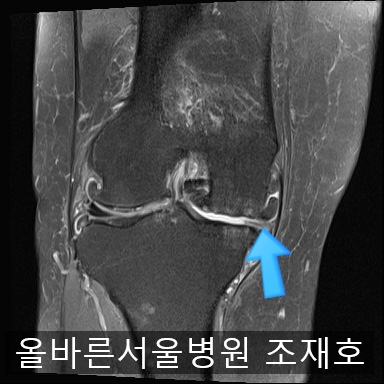

为了掌握具体情况拍了MRI。

髌骨关节虽有炎症,但仍保留相当一部分软骨。

内侧关节软骨几乎不见,软骨板也受损严重。软骨损伤部位充满关节液。

软骨板损伤严重

虽然前方十字韧带粘液样变性,但稳定性无异常

后方十字韧带无明显异常。